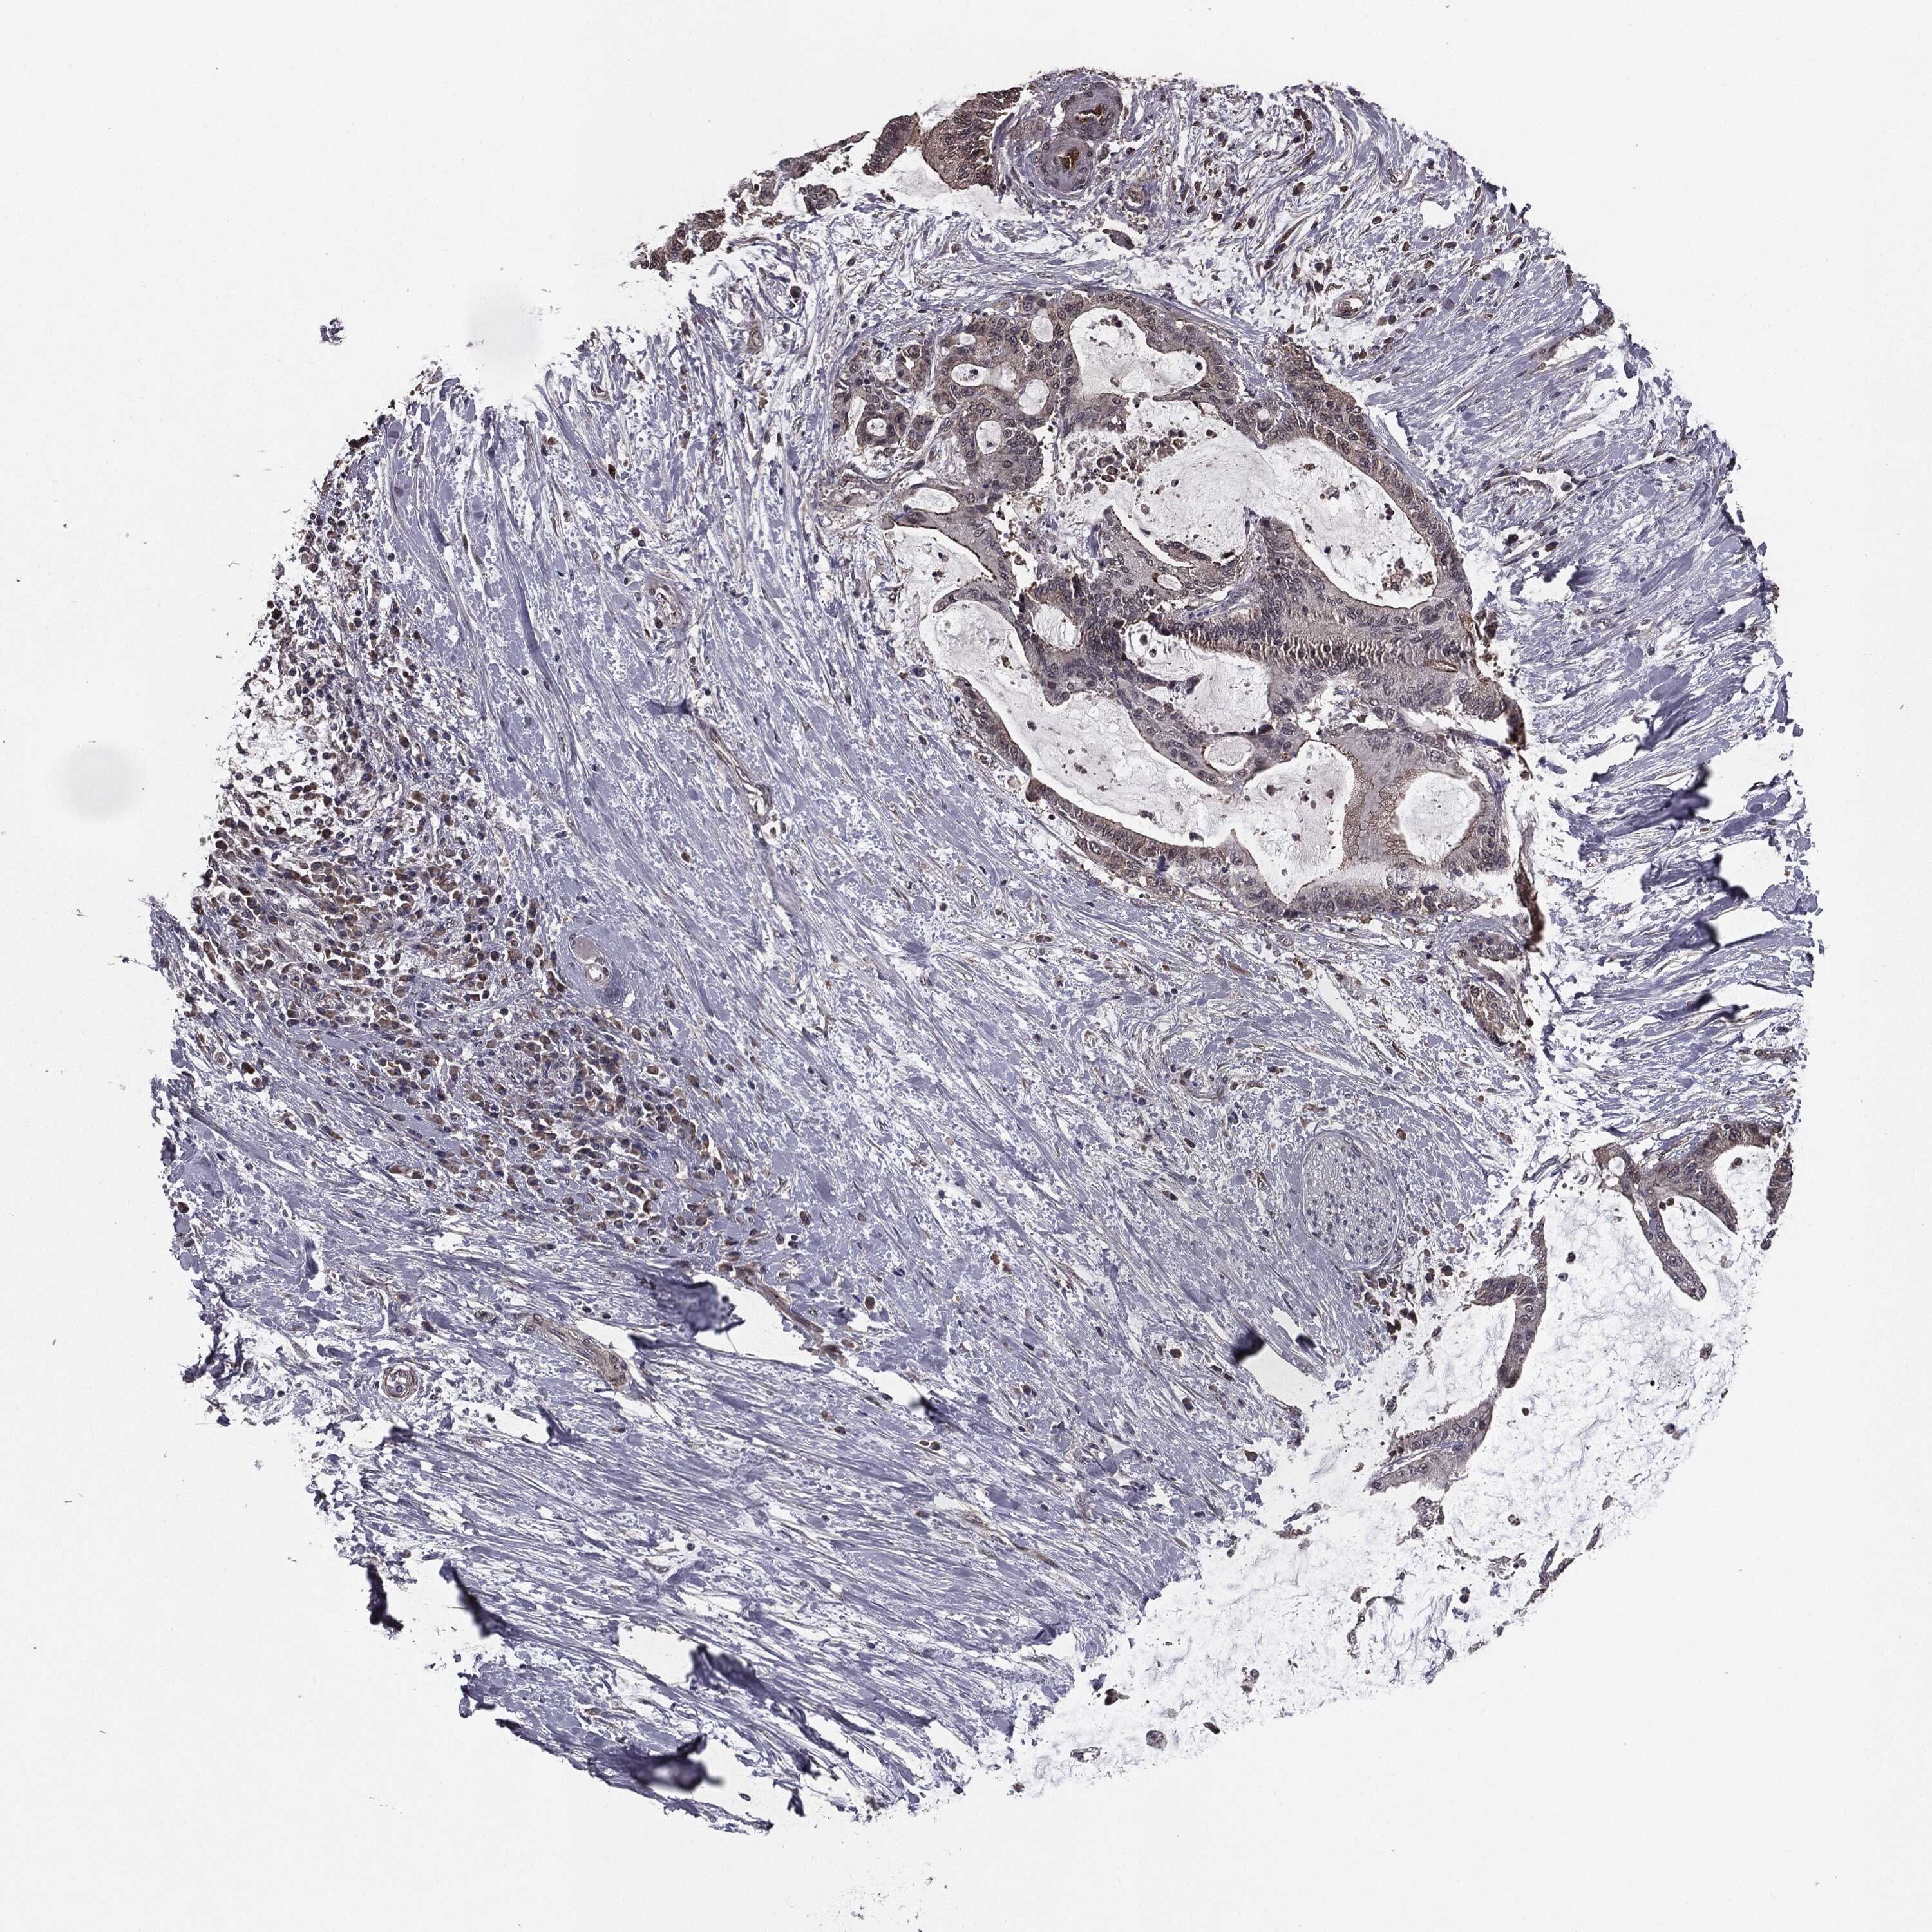

LIVER CANCER - Protein expressioni

A mouse-over function shows sample information and annotation data. Click on an image to view it in a full screen mode. Samples can be filtered based on level of antibody staining by selecting one or several of the following categories: high, medium, low and not detected. The assay and annotation is described here.

Note that samples used for immunohistochemistry by the Human Protein Atlas do not correspond to samples in the TCGA dataset.

Antibody stainingi

Antibody staining in the annotated cell types in the current human tissue is reported as not detected, low, medium, or high, based on conventional immunohistochemistry profiling in selected tissues. This score is based on the combination of the staining intensity and fraction of stained cells.

Each image is clickable and will lead to virtual microscopy that enables deeper exploration of all samples and also displays staining intensity scores, fraction scores and subcellular localization as well as patient and tissue information for each sample.

Antibody HPA052606

Antibody HPA077139

Staining

High

Medium

Low

Not detected

Intensity

Strong

Moderate

Weak

Negative

Quantity

>75%

75%-25%

<25%

None

Location

Nuclear

Cytoplasmic/membranous

Cytoplasmic/membranous,nuclear

Carcinoma, Hepatocellular, NOS

Cholangiocarcinoma